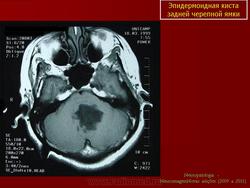

С 1985 по 2000 г.г. в НИИ нейрохирургии им. Н.Н. Бурденко обследовано и оперировано 78 больных с эпидермоидными кистами задней черепной ямки. Изучен клинический симптомокомплекс и КТ, МРТ картина эпидермоидных кист задней черепной ямки.

Разработан метод радикального удаления эпидермоидных кист задней черепной ямки. Выработаны этапы и тактика хирургического лечения. У 81.25%. больных было осуществлено тотальное удаление опухоли. В остальных случаях была оставлена часть капсулы из-за её тесной взаимосвязи с окружающими нейроваскулярными структурами.

Качество оперативного лечения оценивалось изучением динамики неврологического статуса, данных КТ, МРТ, как до операции, так и после операции на разных его стадиях. Современные радиологические исследования и микрохирургическая техника полностью обеспечивает радикальное удаление эпидермоидных кист с хорошим после операционным результатом.